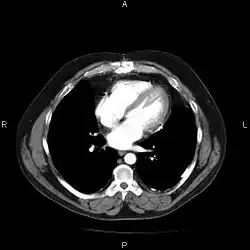

A picture archiving and communication system (PACS) is a medical imaging technology which provides economical storage and convenient access to images from multiple modalities (source machine types).[1] Electronic images and reports are transmitted digitally via PACS; this eliminates the need to manually file, retrieve, or transport film jackets, the folders used to store and protect X-ray film. The universal format for PACS image storage and transfer is DICOM (Digital Imaging and Communications in Medicine). Non-image data, such as scanned documents, may be incorporated using consumer industry standard formats like PDF (Portable Document Format), once encapsulated in DICOM. A PACS consists of four major components: The imaging modalities such as X-ray plain film (PF), computed tomography (CT) and magnetic resonance imaging (MRI), a secured network for the transmission of patient information, workstations for interpreting and reviewing images, and archives for the storage and retrieval of images and reports. Combined with available and emerging web technology, PACS has the ability to deliver timely and efficient access to images, interpretations, and related data. PACS reduces the physical and time barriers associated with traditional film-based image retrieval, distribution, and display.

Most PACS handle images from various medical imaging instruments, including ultrasound (US), magnetic resonance (MR), Nuclear Medicine imaging, positron emission tomography (PET), computed tomography (CT), endoscopy (ES), mammograms (MG), digital radiography (DR), phosphor plate radiography, Visible Light Photography (VL), Histopathology, ophthalmology, etc. Additional types of image formats are always being added. Clinical areas beyond radiology; cardiology, oncology, gastroenterology, and even the laboratory are creating medical images that can be incorporated into PACS. (see DICOM Application areas).